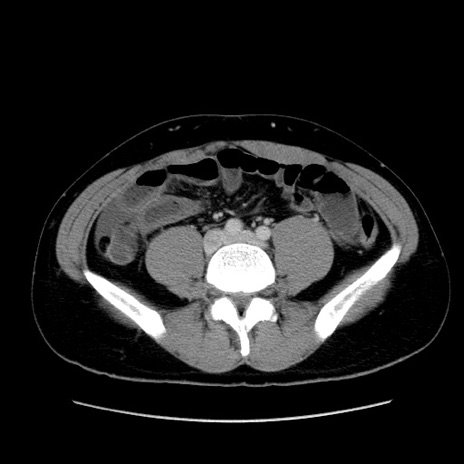

症例36(横断像)

【症例】20歳代 男性

【主訴】心窩部痛

【現病歴】今朝より上腹部痛あり。一旦軽快していたが再度出現したため救急要請。昨日夕に白身の魚を含む刺身を食べた。

【身体所見】BP 136/89mmHg、HR 74/min、BT 37.0℃、腹部:膨満、軟、心窩部に圧痛あり。反跳痛なし、筋性防御なし、腸雑音やや亢進あり。

【データ】WBC 17700、CRP 0.48